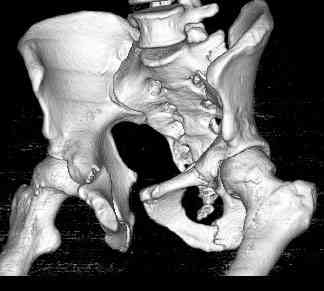

Уважаемые коллеги! опять вопрос по повреждению таза. Больной получил производственную травму 10 дней назад - удар балкой около 3 тонн в область верхней трети правого бедра и лона.

Был диагностирован перелом "типа бабочки" и повреждение уретры. Сделана цистостома. У насв отделении 3 дня. Имеется огромная флюктуирующая гематома с "галифе"-образной деформацией обеих бедер. Пнкционно эвакуировали в несколько приемов из подфасциальных полостей на бедрах около 3 литров геморрагического отделяемого с последующей эластической компрессией. При пункциях выявлено сообщение полостей на бедрах - видимо через поравннуюдиафрагму дна и полость таза - при удалении крови справа уменьшался объем левого бедра. Какой то активности проявялять покабоимся - аппаратная фиксация через отслоенные ткани представляется чреватой нагноением, открытая фиксация в условиях такой гематомы тоже не радует. Хотелось бы услышать ваше мнение

можно полечить в 2 этапа:как правило в области гребней гематомы все же не бывает, если гребни "свободны", то можно ограничиться на первом этапе передней рамой, вводя стержни через них (повреждение ротационно-нестабильное), затем после лечения отслаивающего повреждения Morel-Lavallee, выполнить открытую репозицию, внутреннюю фиксацию, возможно вместе с урологами. Тактику возможного лечения этой

гематомы прилагаю.

Следующим этапом через 5-6 дней приступаем к фиксацию повреждения таза, иначе прооперериванные на фоне Morel-Lavallee повреждения осложняются инфицированием послеоперационной раны.

18.12. - отдельное спасибо еще раз А.В.Рункову- больного оперировали (А.В.Рунков) - произведен остеосинтез аппаратом - фиксация за крылья, два стержня в лонные кости и репозиция (почти полная) снимки будут чуть позже.

Дренировали отслойки на бедрах с их санацией. В правой ягодичной области сформировалась зона некроза. Больной "подвешен" за аппарат.